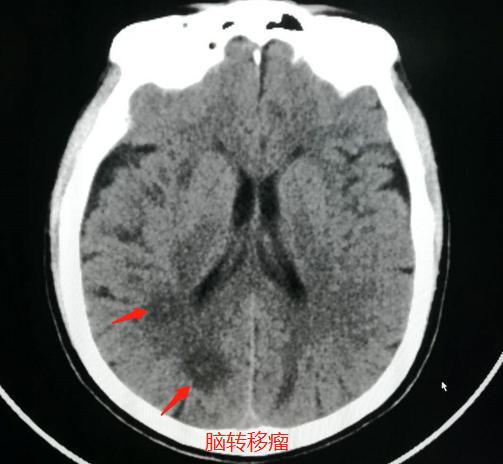

病例2,女性患者,67岁,头晕一周行脑CT检查:

发现脑内多发类圆形低密度影,内部似乎还有稍高密度小结节,可疑脑转移瘤,于是进一步肺CT检查:

果然发现了右侧肺癌脑转移,伴有胸膜牵拉和增厚。